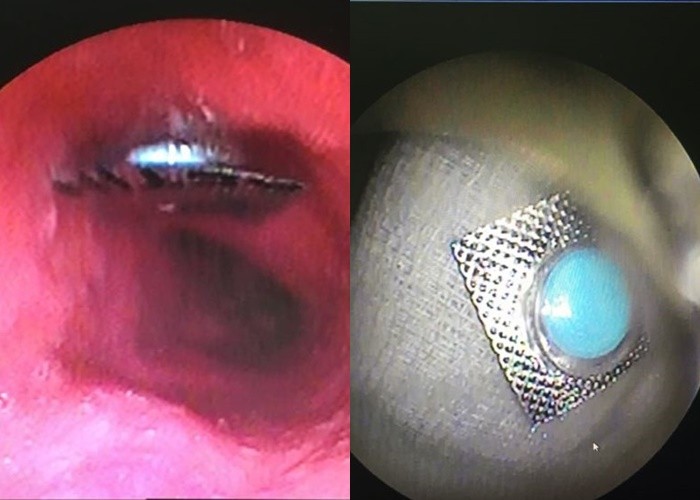

Hình ảnh nôi soi cho thấy viên thuốc còn nguyên vỏ trong bụng bệnh nhân. Ảnh: BV

Bệnh nhân Đ.U.L. đến Khoa cấp cứu, BV Quận 11 trong tình trạng đau tức ngực do nuốt phải thuốc còn nguyên vỏ, vào ngày 25/12. Bệnh nhân lập tức được nội soi, kết quả cho thấy viên thuốc còn nguyên vỏ có kích thước 9 x 9mm, hình vuông, cạnh sắc bén như dao đang nằm ở đoạn giữa thực quản. Nếu không cấp cứu lấy viên thuốc kịp thời, có thể gây nguy cơ thủng thực quản, dẫn đến tử vong.

Ngày 26/12, BV Quận 11 đã tiến hành lấy vỏ thuốc cho nữ bệnh nhân. Đơn vị Nội soi đã phối hợp với bác sĩ Khoa Gây mê hồi sức, tiến hành tiền mê để nội soi. Đồng thời, các bác sĩ đã dùng chụp dị vật bằng silicon để bọc dị vật lại, tránh gây chảy máu và làm thủng thực quản khi kéo dị vật ra ngoài.